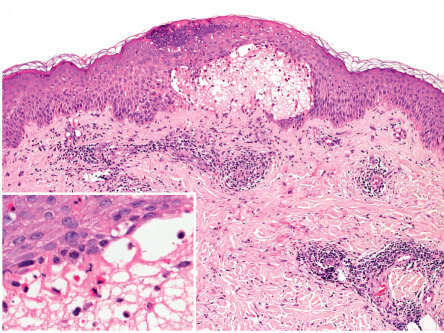

Pathology

The classic histologic finding of a subepidermal vesicle is seen in the minority of patients. Instead, a nonspecific mixed cellular infiltrate containing a variable number of eosinophils is more common. The presence of eosinophils is the most constant histologic feature of pemphigoid gestationis ( Fig. 27.2 ).